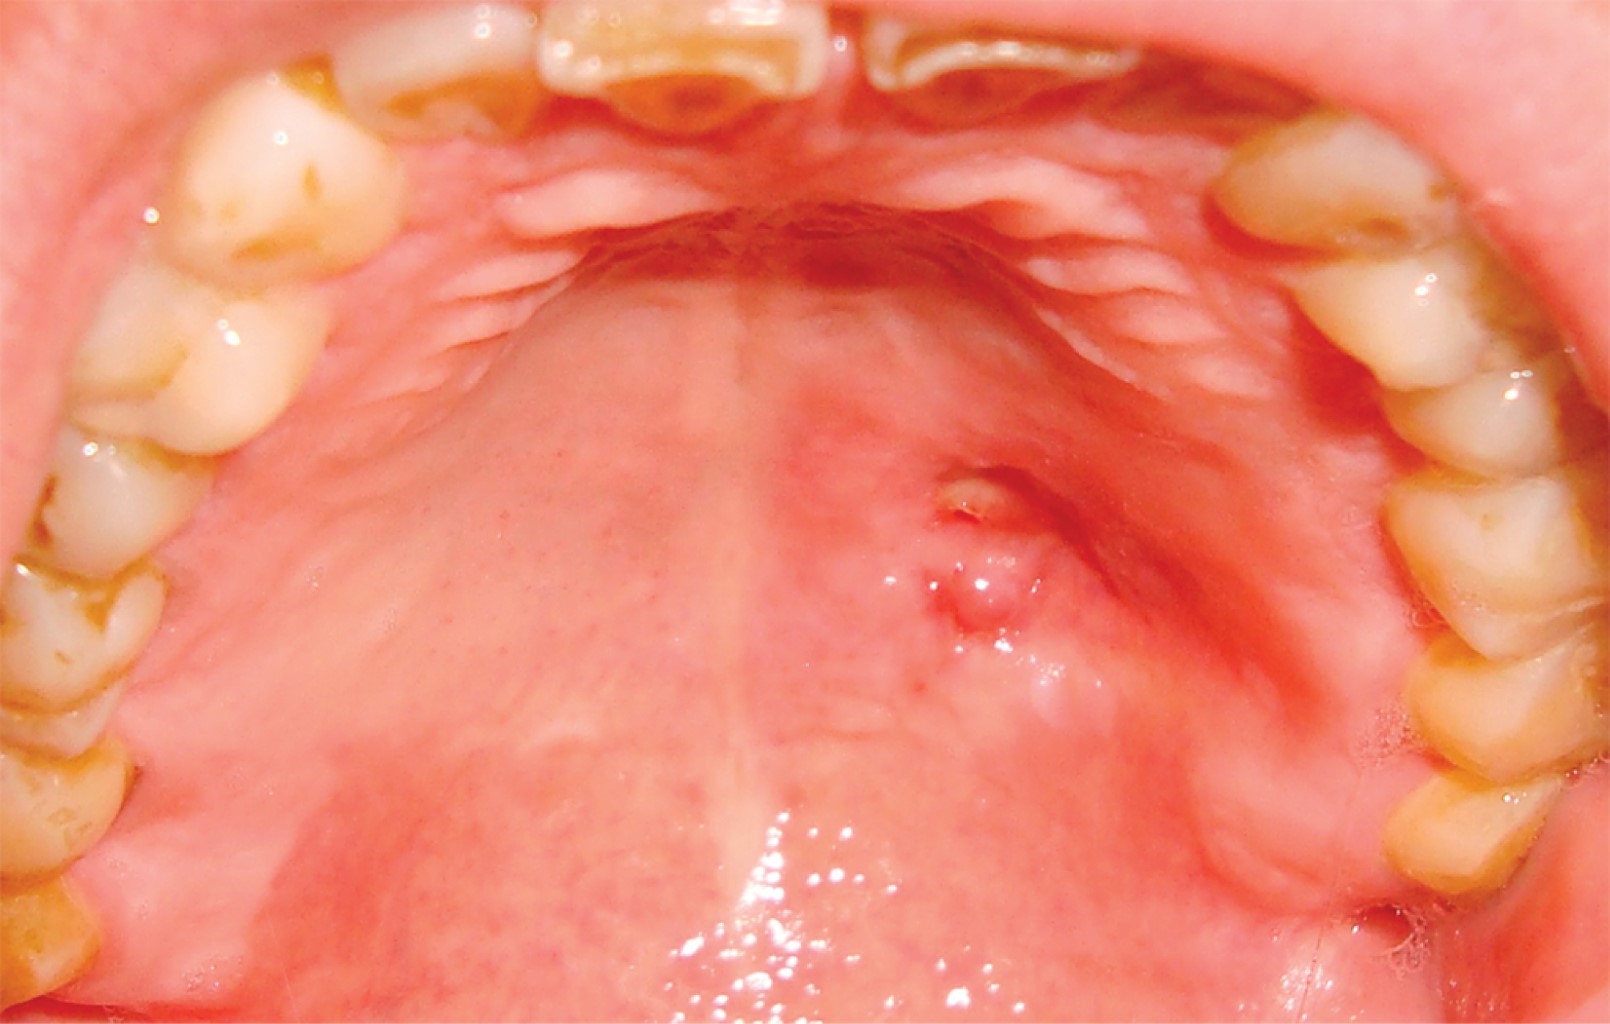

El paciente es remitido con informe de biopsia incisional, la cual detalla mucosa revestida por epitelio escamoso con ligera acantosis y foco de exocitosis linfocitaria. Corion con infiltrado inflamatorio linfoplasmocitario y presencia de proliferación fusocelular entremezclada con fibrosis que comprime estructuras vasculares (Figura 2). Se realizaron técnicas de inmunomarcación con vimentina, actina, demina y CD31, resultó la proliferación descrita positiva con vimentina y actina, en tanto que negativa para desmina y CD31; posteriormente, se arribó al diagnóstico de miofibroma. Bajo anestesia general balanceada se realizó la enucleación marginal de la lesión (Figuras 3 y 4). El análisis histopatológico de la pieza quirúrgica confirma el diagnóstico prequirúrgico. No se evidenciaron signos de recurrencia de la enfermedad luego de 24 meses de controles (Figura 5).

Figura 5